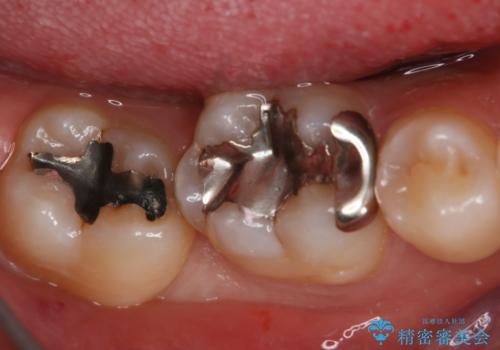

- 右上下6番の銀歯のやり変えを希望された患者様です。

切削量・形態を考慮し、上はセラミッククラウン、下はセラミックインレーでの治療を選択しました。

上はう蝕が歯頚部まで達していたのでクラウンでの治療を選択しました。

銀歯直下もう蝕が進行していたので全て除去した上でCRにて裏層しています。

下はクラウンほど切削量が多くないと判断し、インレーでの治療を選択しました。